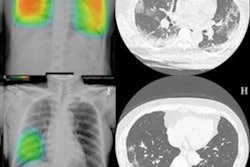

The software is currently in use at several hospitals and clinics throughout Korea. Free demos of Lunit's Insight for mammography and Insight for chest radiography and are available online at the company website.